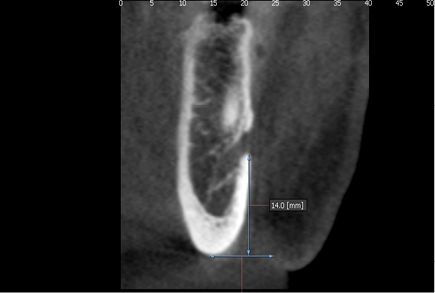

The distances from the upper and lower cortical areas of the mental foramen to the alveolar crest and the mandibular basal bone respectively were analyzed, as well as the size of the hole on the transaxial cut. There we considered the distance between the upper and lower cortical areas of the structure, and the measurements were classified into ranges (Figures 1 and 2).

Fig. 1: Location of mental foramen on the transaxial plane

The distances from the upper and lower cortical areas of the mental foramen to the alveolar crest and the mandibular basal bone respectively were analyzed, as well as the size of the hole on the transaxial cut. There we considered the distance between the upper and lower cortical areas of the structure, and the measurements were classified into ranges (Figures 1 and 2).

Fig. 1: Location of mental foramen on the transaxial plane